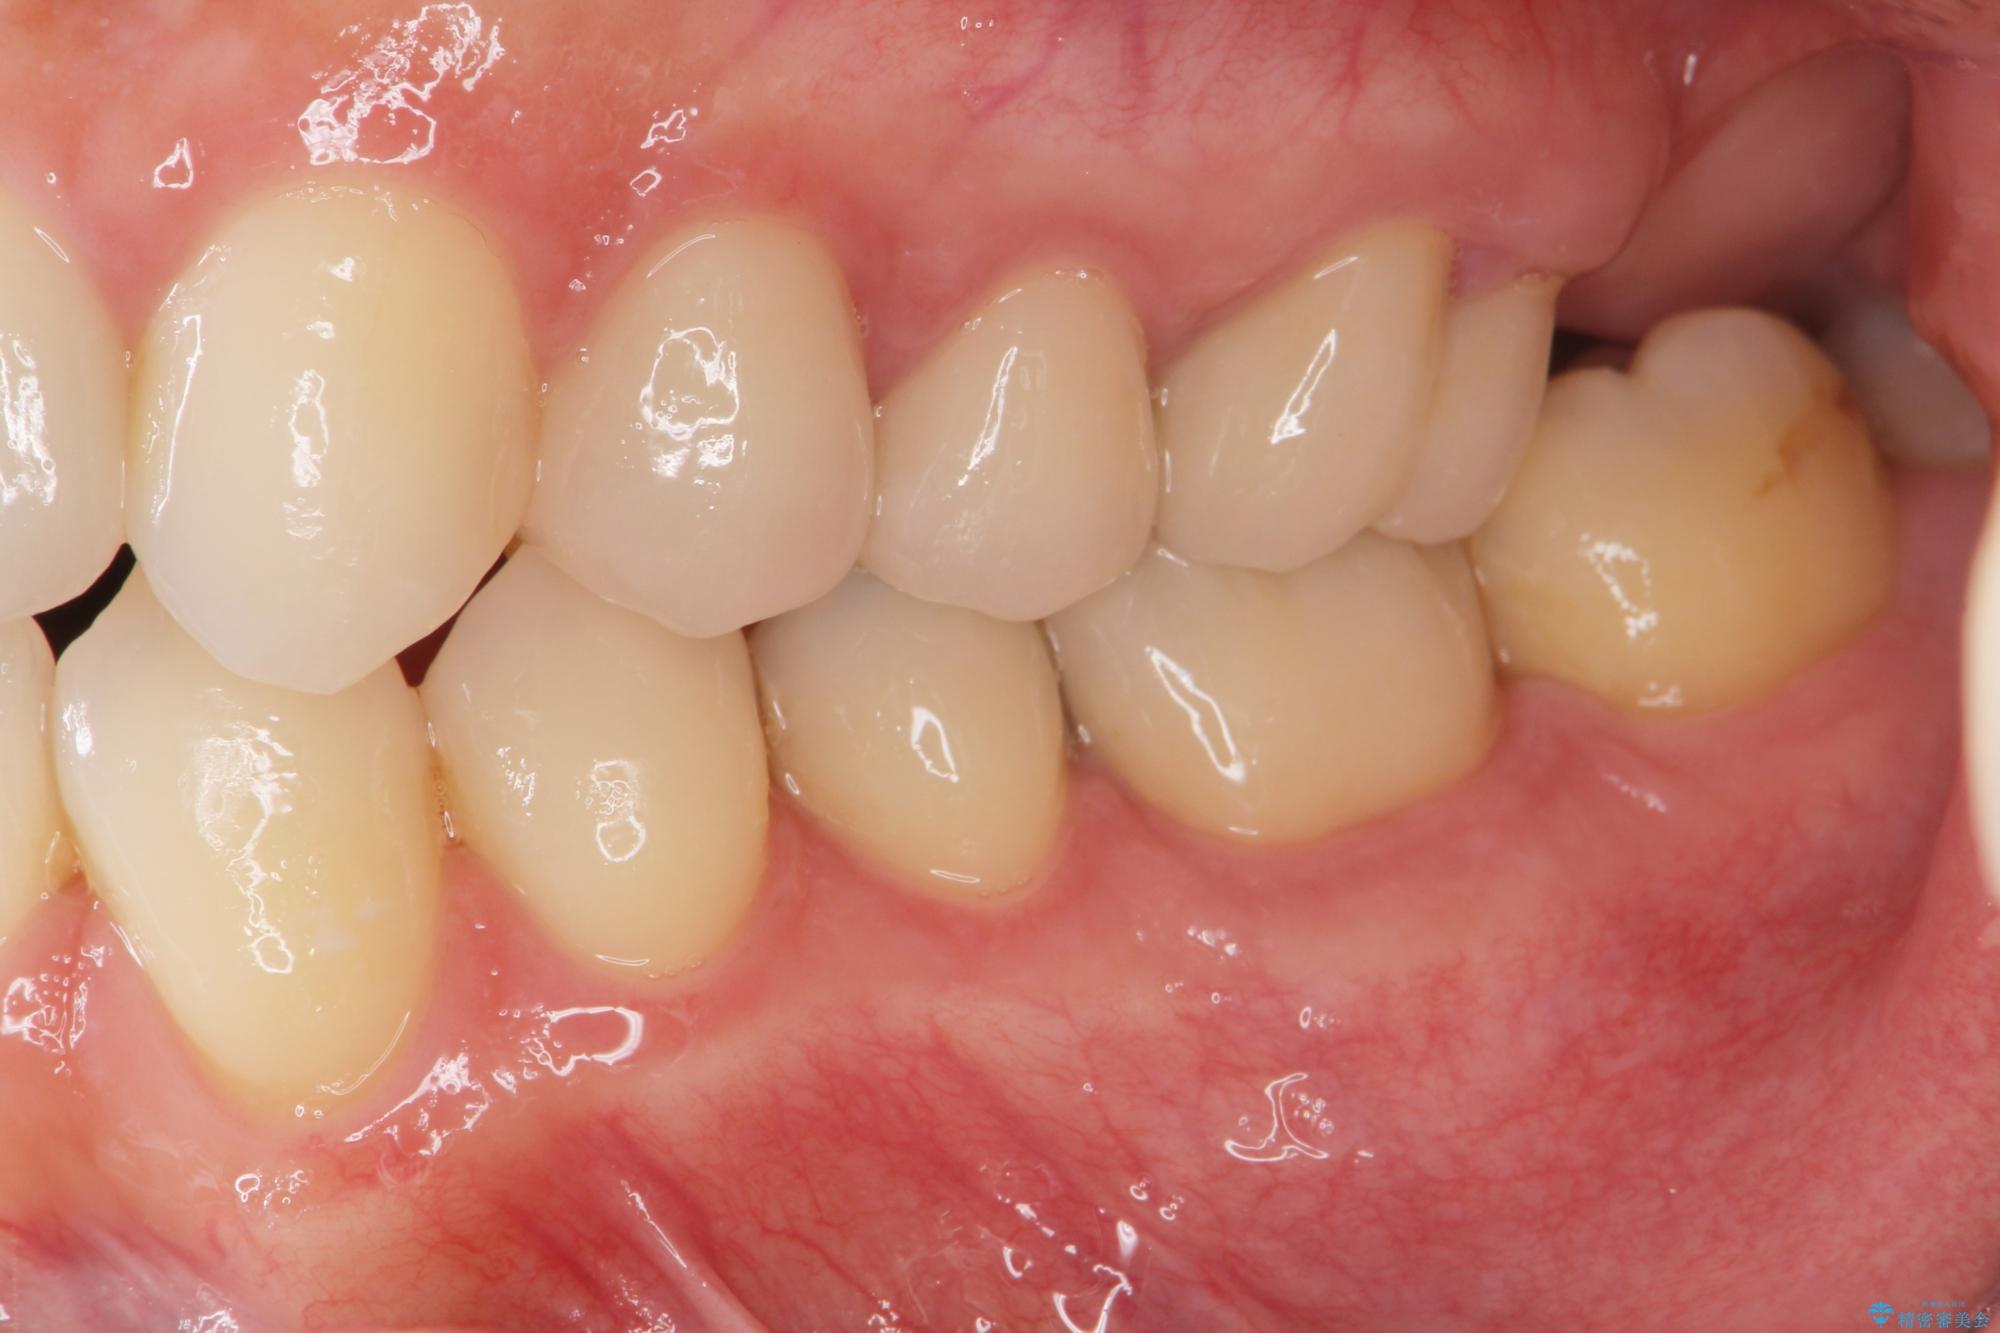

矯正と虫歯のセラミック治療 総合歯科治療の実践

- 突き出た前歯の角度の改善と虫歯治療の改善を求めて来院されました。

虫歯を除去したのち、マウスピース矯正治療を行い、歯並びやがたつきを改善したのち、セラミックに置き換えることで審美性の向上を計画します。